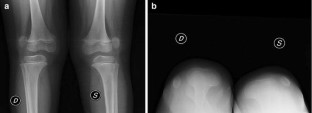

Fig. 2